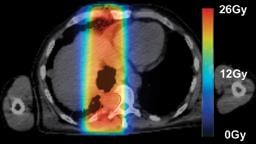

Radiation therapy is an important clinical option for the alleviation of pain and suffering for cancer patients and is used for palliative treatments to prevent pathologic bone fractures or tumor-induced obstructions, bleeding and pain that is resistant to other treatments. However, standard palliative radiation therapy treatment techniques often offer poor conformality and expose large volumes of normal tissues to radiation-induced toxicities, causing significant side effects for an already ill patient with a limited life expectancy.